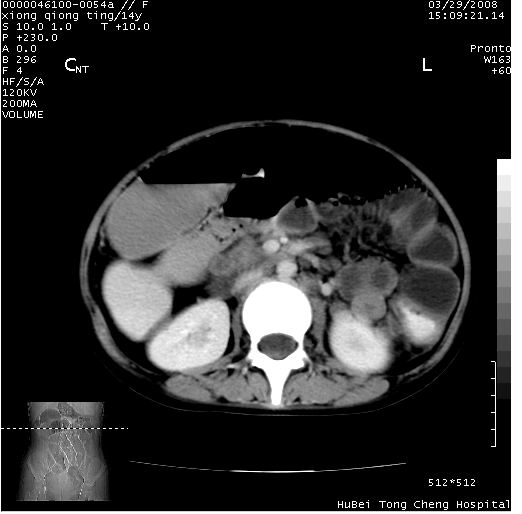

中下腹及盆腔ct轴位平扫+增强扫描(层厚10mm,螺距1.0,重建间隔10mm),图像如下:

(注:患儿检查当日上午9时口服胃肠道对比剂,下午3时许行ct扫描检查,未行对比剂直肠保留灌肠,检查当日患儿腹泻)

中下腹及盆腔ct轴位扫描(ps+ce)提示:腹部肠管明显充气扩张,并见数个不同宽度之气液平面;疑不全性肠梗阻或肠郁张。临床会诊考虑为患儿腹泻,肠郁张所致;后来未经特殊处理,患儿大便恢复正常,亦无腹胀。